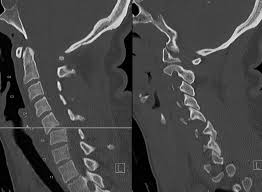

Tassement De Vertebres Definition Symptomes Et Traitements

Tassement De Vertebres Definition Symptomes Et Traitements from static.passeportsante.net